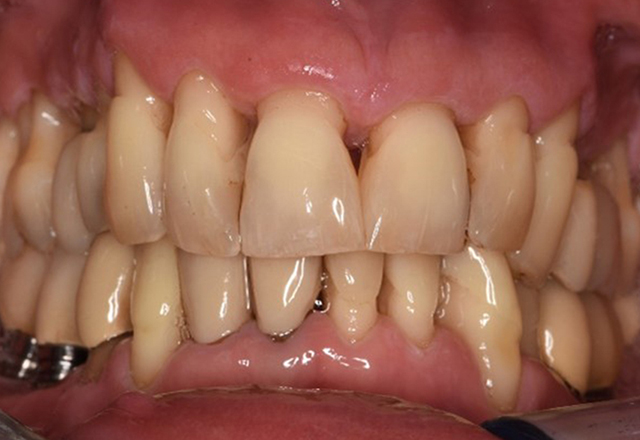

Pacient sănătos cu boală parodontală incipientă

Pacientul în vârstă de 68 de ani nu are nicio afecțiune generală și nu ia niciun medicament care ar putea fi relevant pentru sănătatea sa orală, iar stilul său de viață nu prezintă niciun risc special. Pacientul are două implanturi dentare (cadranul 3, de cinci ani) și un caz anterior de boală parodontală (stadiul IV, gradul B) cu pierderea dinților. În prezent, condițiile parodontale sunt stabile. Cu toate acestea, parodontoza crește semnificativ complicațiile biologice ale implanturilor și există riscul de pierdere a implanturilor (21). Se pot determina patru recomandări pentru ședința de profilaxie. mai multe